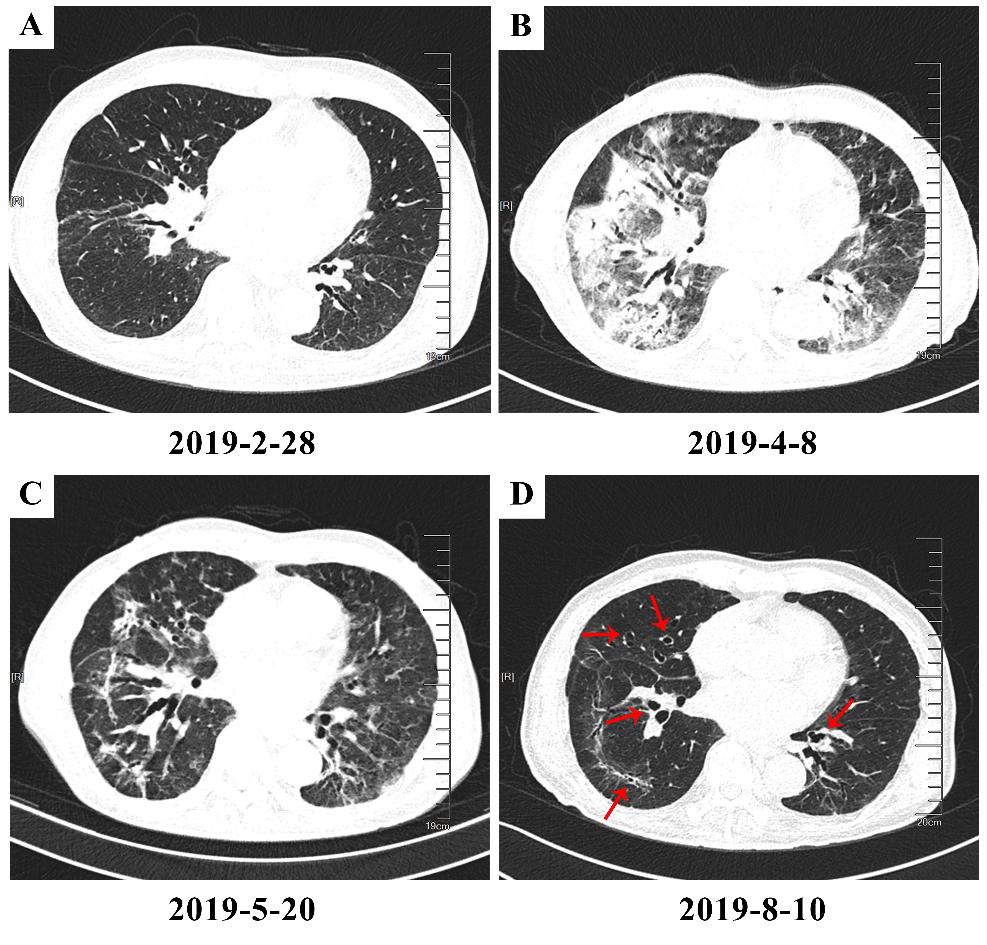

在51例影像可评估CIP患者中,94.1%的患者表现为磨玻璃影和/或斑片影,其中14.6%的患者伴有支气管充气征;其余常见影像学表现还包括条索影、实变影、弥漫性结节病变等。尽管表现各异,但在共14名至少有2个时相CT图像用于观察变化的患者中我们发现,各阶段之间的变化主要为病灶吸收,其主要影像学特征没有明显的变化,但在3名患者中观察到纤维化改变相关特征(如牵引性支气管扩张)的增加。从急性期到慢性期CIP影像学典型变化如下图。